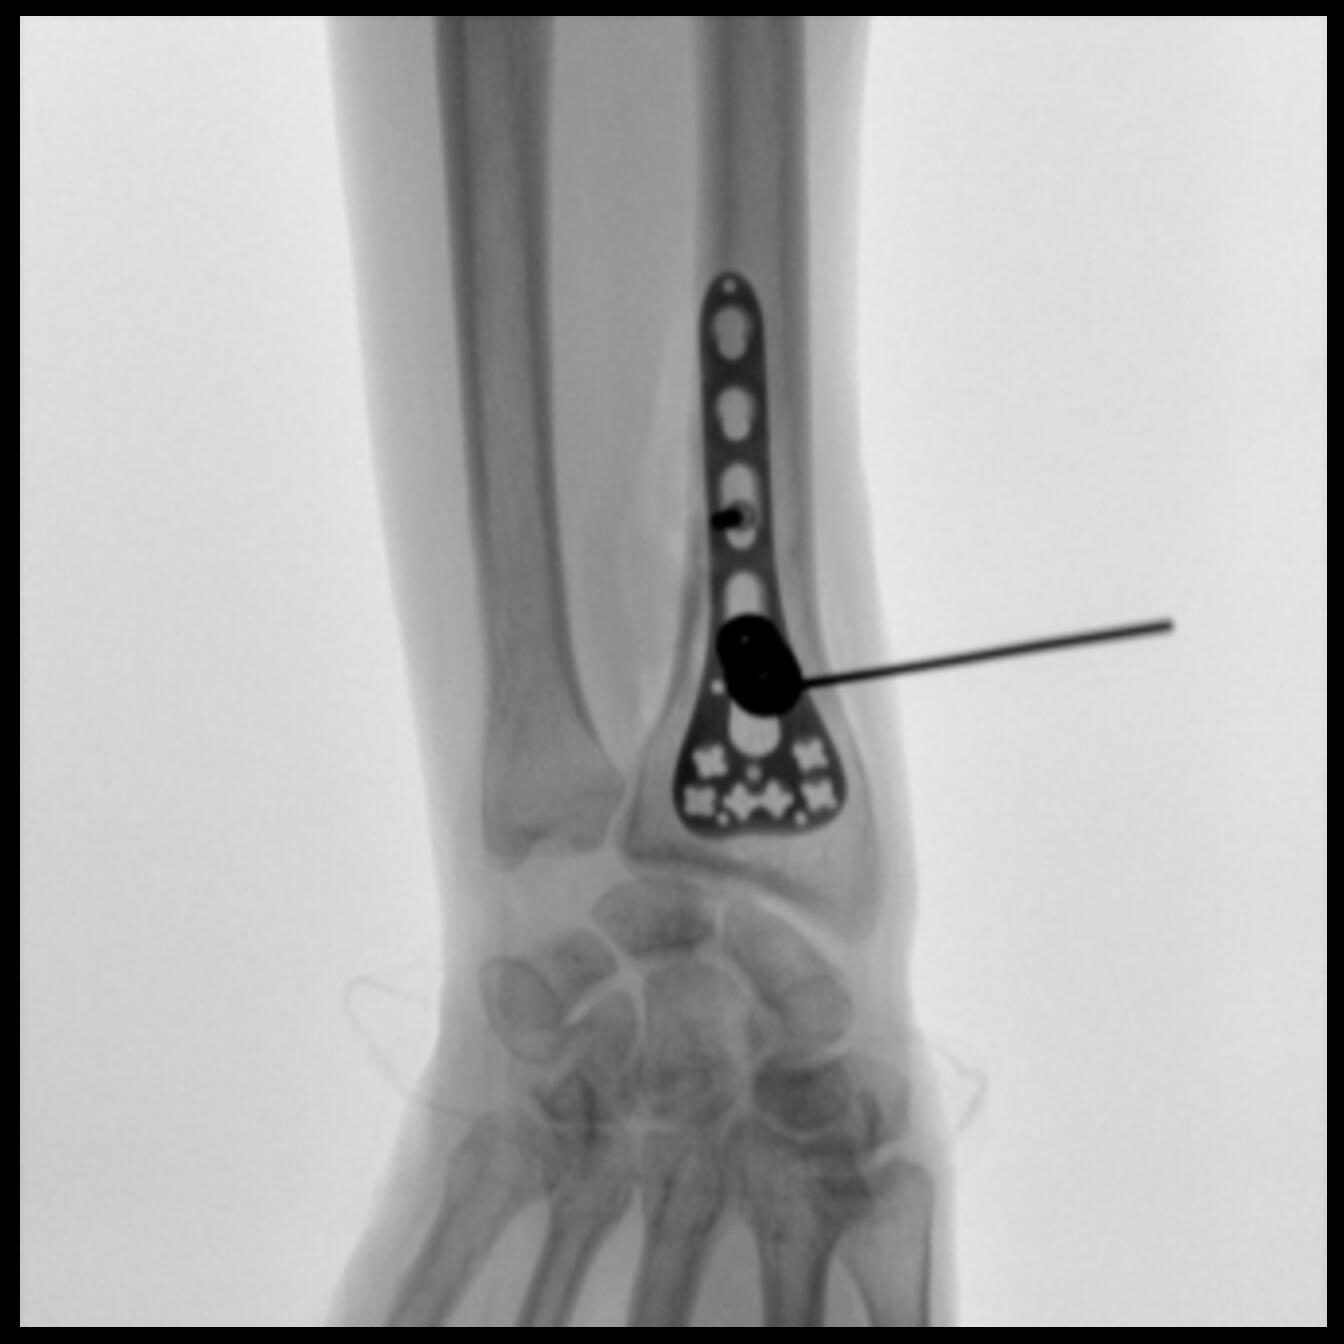

PLX118F-Plus配備了兩種平板尺寸,大尺寸動(dòng)態(tài)平板探測(cè)器成像面積較傳統(tǒng)平板探測(cè)器提升了25%以上,在視野需求大的手術(shù)中,便于醫(yī)生更好定位病灶點(diǎn),規(guī)劃手術(shù)方案,減少因視野范圍不足而多次透視、點(diǎn)片造成的不便。